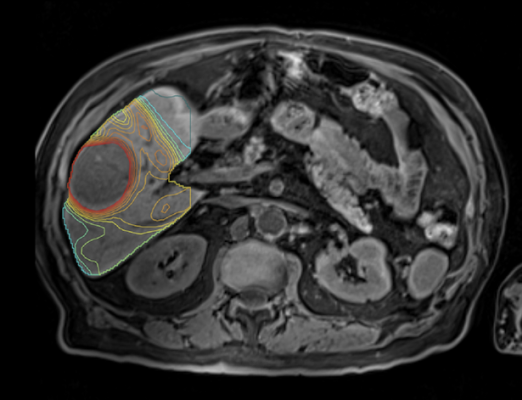

At TeleDaaS, a team of leading dosimetry practitioners leverage proprietary software from Mirada Medical, LTD, which integrates with standard imaging technology, to support clinical research organizations in clinical trial design, execution and the development of new targeted radiation therapies. TeleDaaS’s platform is highly scalable for clinical trials and offers CROs and pharmaceutical companies flexibility with regard to hiring in-demand dosimetrists.

Mirada’s personalized, or multi-compartment, dosimetry technology has been used in multiple clinical trials to dramatically improve clinical outcomes, including DOSISPHERE-1 which compared personalized dosimetry with standard dosimetry. The life expectancy of patients on the personalized dosimetry arm of the trial increased to 26.6 months from 10.7 on the standard dosimetry arm of the trial. The benefits of personalized dosimetry were so stark that the trial was cut short because it was deemed unethical to assign patients to the standard dosimetry arm of the trial.